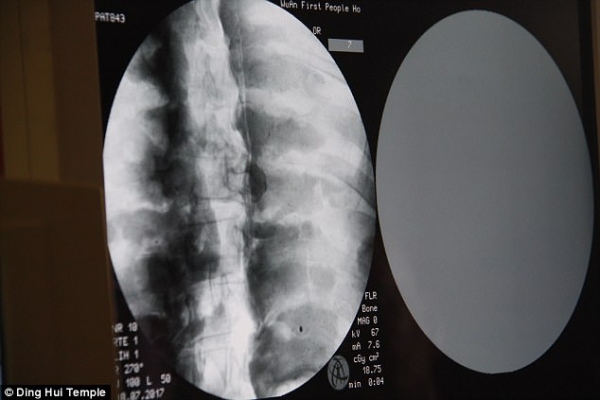

但是經過千年大家才知道這尊佛像裏頭的卻是….根據了解有研究學者透過X光還有XT掃描檢驗,發現驚人的秘密!這是貨真價實的木乃伊,但沒想到最難保存的大腦竟然都還留著!?

當地學者受訪表示:「我們在掃描後發現,他的骨頭跟一般人的一樣完整。」

「上額、上面的牙齒、肋骨、脊椎骨、連關節全部都還在。真的是很驚奇的景象」